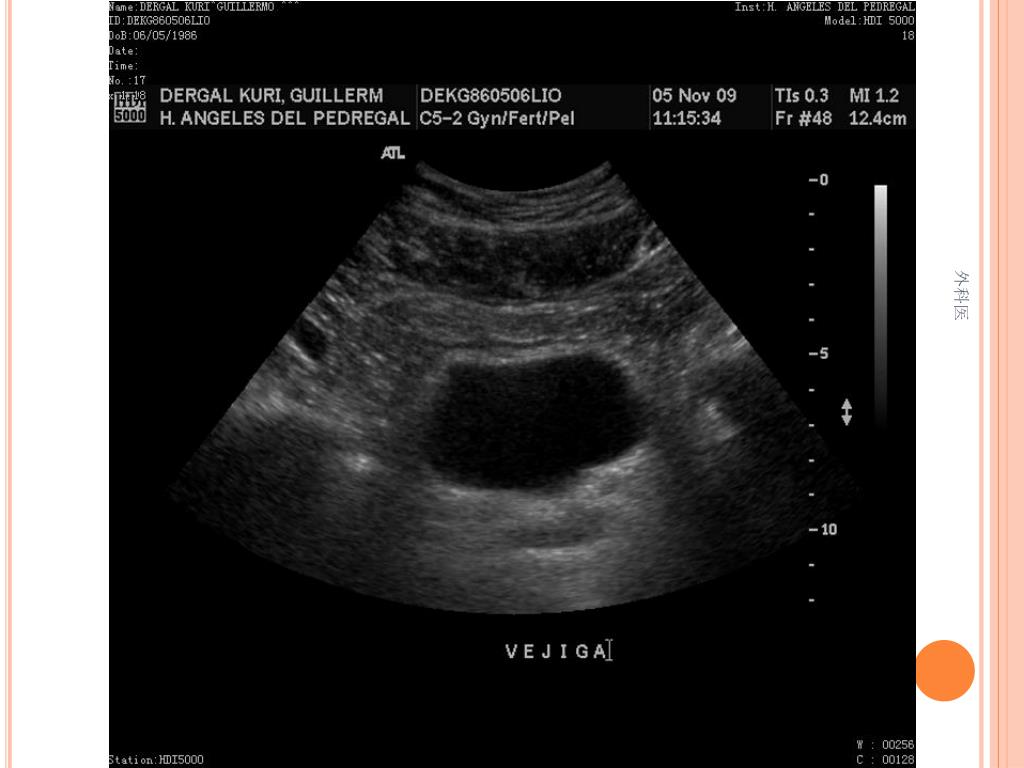

44. Tips • Leucocitos Mas de 20000/ml • Mas de 20% de la apéndices no se llenan con el bario por enema. • USG sensibilidad del 85% y Especificidad de mas 90% para Apendicitis Aguda. • TAC de Abdomen cortes de 5mm, sensibilidad y especificidad del 90% para dolor abdominal. • Analisis de 75000, taza de apendice negativa de 6% Hombres y 13% Mujeres 外科医